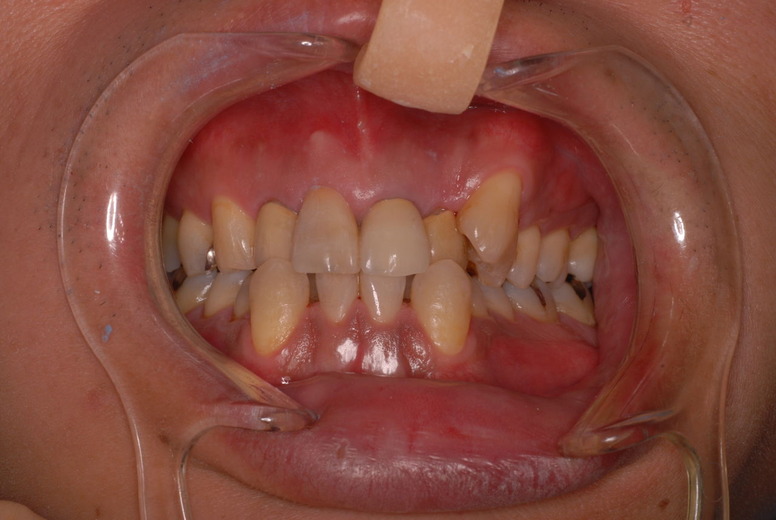

親知らずを取ることを嫌がる方が多いのですが、もし親知らずとその隣の14歳大臼歯の間に虫歯ができたり歯周病を罹患した場合、どれほど治療が大変で再発も起こりやすいか理解できない方がおおいのです。

写真左下の親知らずが痛くなり抜歯しました。その後歯茎を除去して虫歯を露出させる処置を二回ほどしています。

治療の成功率は極めて悪くすぐ再発しやすいのです。